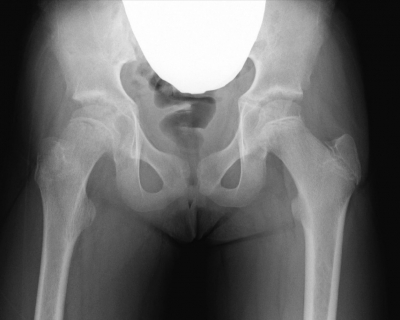

12 歳の女児。右大腿部から膝の痛みを主訴に来院した。1か月前に友人とぶつかって転倒した後から、痛みが出現した。様子をみていたが痛みが軽快しないため受診した。身長 148 cm、体重 50 kg。体温 36.3 ℃。右股関節前方に圧痛を認める。 歩行は疼痛のため困難である。右股関節可動域は屈曲と内旋とに制限がある。血液生化学所見に異常を認めない。股関節のエックス線写真を示す。

初期対応として適切なのはどれか。